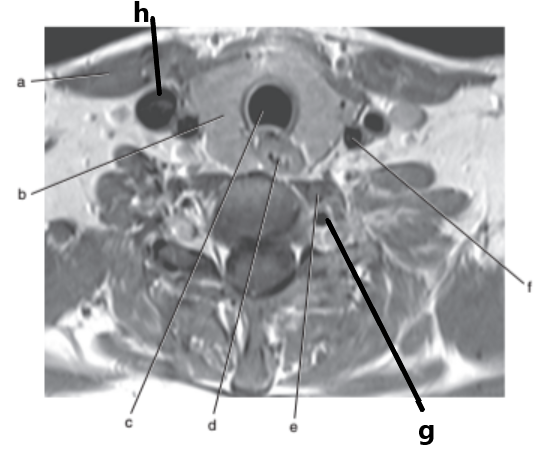

What imaging plane is this ?

transverse

What is letter g ?

Common carotid artery

What is letter h ?

Internal jugular vein

What is letter f ?

Spinal cord

Vocal cords